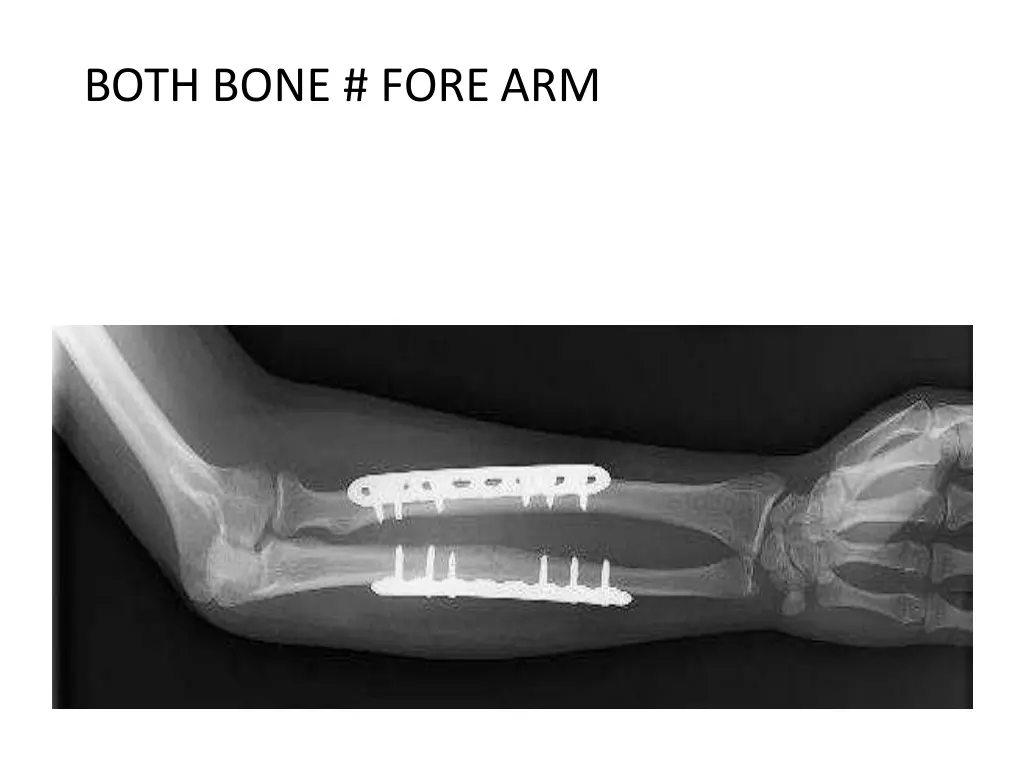

5. ORTHOPAEDIC CONDITIONS IN INPATIENTS UPPER LIMB SUPRA CONDYLAR # HUMERUS BOTH BONE # FORE ARM COLLES #

6. BOTH BONE # FORE ARM